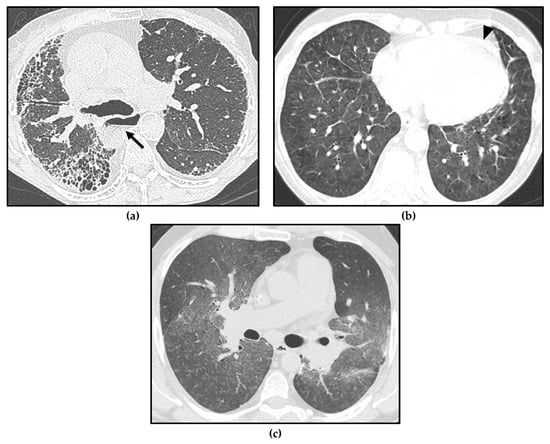

Isolated centrilobular ground-glass nodules can also be found in SSc-PAH [45], making the differential diagnosis with PVOD/PCH very challenging (Figure 5). Moreover, in SSc patients, pulmonary edema due to LHD or acute exacerbation of the underlying ILD, with radiological findings such as PVOD/PCH, can occur.

Figure 5.

Different forms of pulmonary hypertension (PH) in systemic sclerosis (SSc) patients. Interstitial lung disease (ILD) showing a usual interstitial pneumonia (UIP) pattern, with asymmetric distribution of fibrotic abnormalities and honeycombing foci in the subpleural zones, especially in the right middle lobe and right lower lobe (a); note massive esophageal dilation, with the air–fluid level (arrow) and the enlargement of the main pulmonary artery (PA). Pulmonary veno-occlusive disease/ pulmonary capillary hemangiomatosis (PVOD/PCH), with smooth interlobular septal thickening and diffuse ground-glass opacities in the lung bases (b); note the mild pericardial effusion, which may be linked either to serositis or to PH (arrowhead). Pulmonary arterial hypertension (PAH) characterized by profuse bilateral tiny centrilobular ground-glass micronodules (c).

Therefore, a correct clinical–radiological correlation in a multidisciplinary context is required to distinguish between these conditions in SSc patients with PH and to avoid complications.